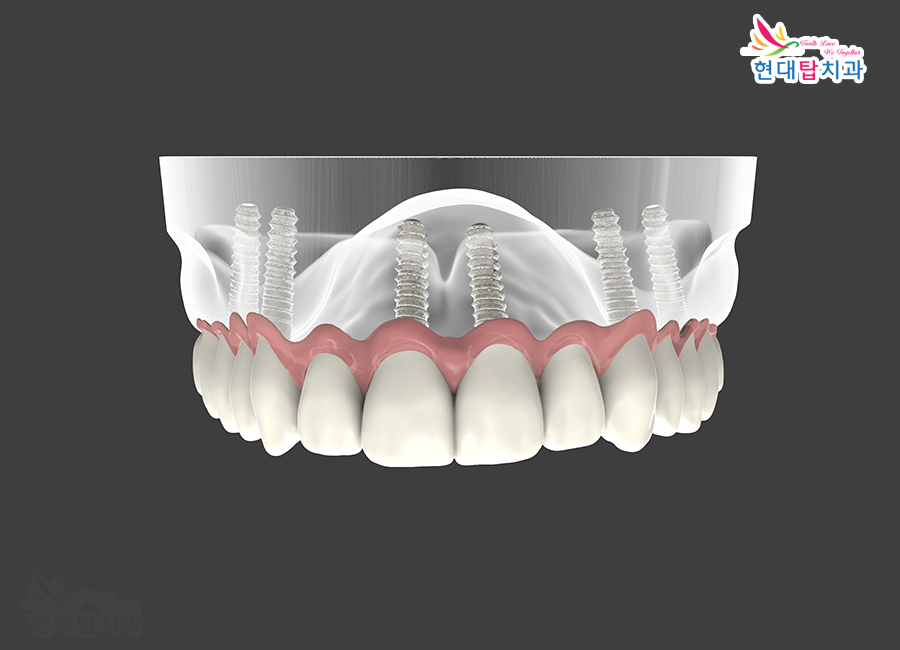

임플란트는 상실한 치아를

대체할 수 있는 치료 방법으로

자연치아와 가장 흡사한 형태와

기능을 가지고 있습니다.

인체에 거부반응이 없는 티타늄으로

만들어진 인공치근을 잇몸뼈에 식립하여

인공치근과 보철물을 연결해 주는

지대주 위에 치아 모형의 최종 보철물인

크라운을 연결하는 과정으로 진행됩니다.